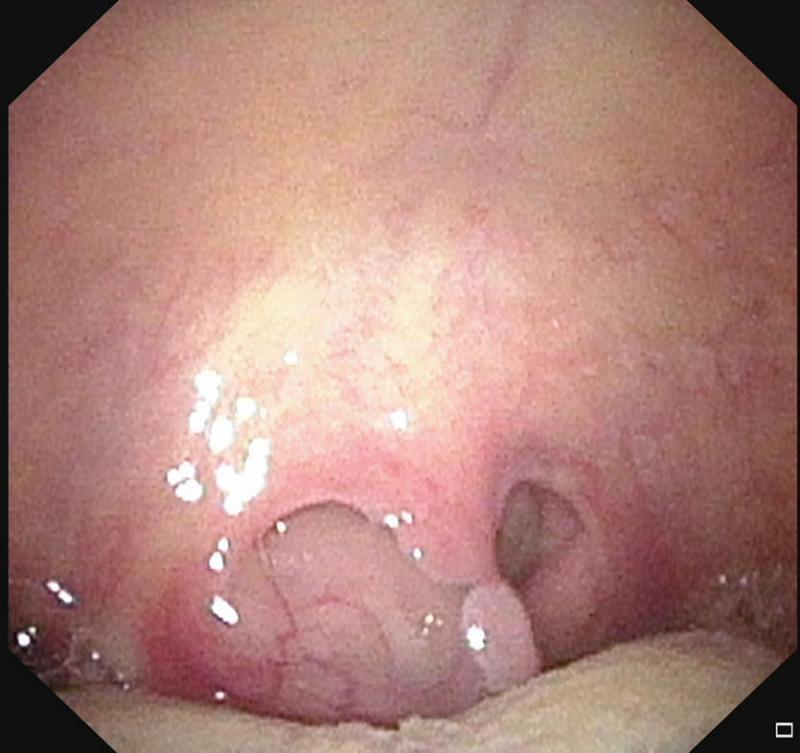

·甲状腺隐藏在舌根里:甲状腺在发育过程中未下降到颈项前的正常位置,而出现于其他部位,称为异位甲状腺。这是一种罕见的胚胎发育异常疾病。甲状腺最常隐藏的部位是舌根中线区,女性多于男性。

如果男女到了十七八岁,甲状腺还未下降到颈项前,睡觉时就容易引发窒息。治疗法是割除甲状腺,病人过后可口服甲状腺素片发挥甲状腺功能。